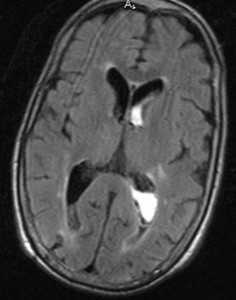

МРТ головного мозга. Аксиальная Т2-взвешенная МРТ типа FLAIR. Внутрижелудочковое кровоизлияние.